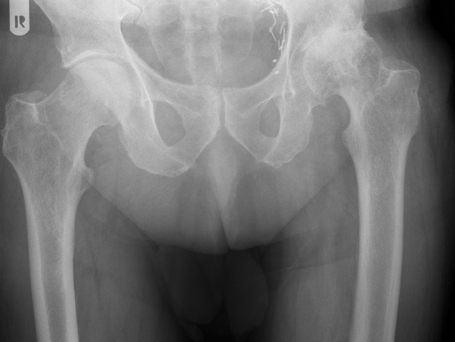

HÜFT-TEP DER PATIENTIN

Linksseitige Coxarthrose, nach Umstellungsosteotomie rechts

Planung Hüft-Endoprothese links

Nach Implantation einer Kurzschaftprothese auf der linken Seite. Die rechte Seite nach Umstellungsosteotomie vor Jahren